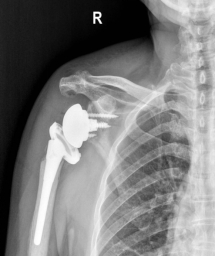

术后X线片